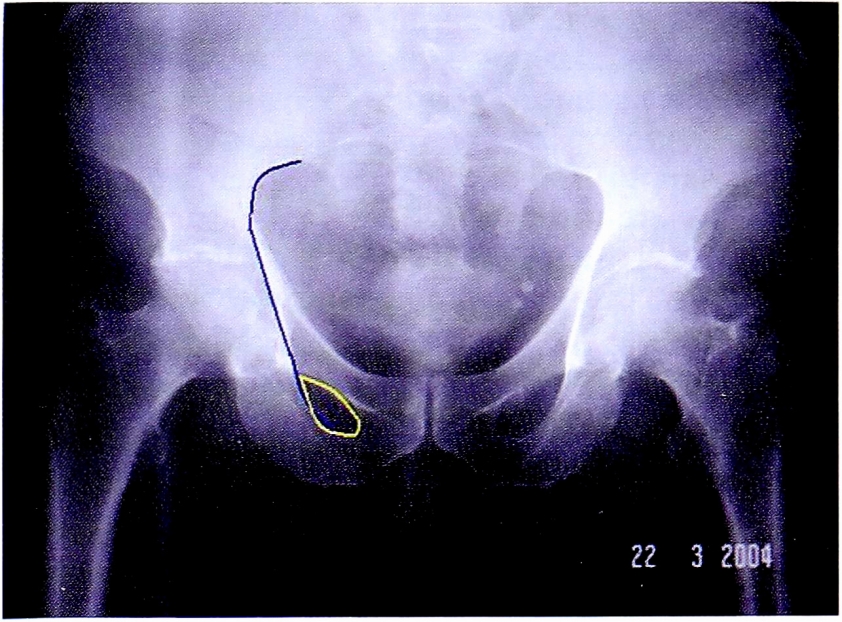

На обзорной рентгенограмме, представленной на рис. 14 достоверно определяется нарушение непрерывности подвздошно-гребешковой и подвздошно-седалищной линии.

Рис. 14. Обзорная рентгенография таза пациента с переломом вертлужной впадины.

Fig. 14. АР pelvic X-ray of patient with acetabular fracture.

С помощью рентгенограммы в косой запирательной проекции, выполненной по методике НМИЦ ТО, диагностирован перелом задней стенки со смещением отдельного фрагмента. Также с помощью прицельного снимка определена целостность контуров запирательного отверстия (рис. 15).

Рис. 15. Рентгенография правого тазобедренного сустава в косой-запирательной проекции, выполнена по методике НМИЦ ТО. Стрелками показан перелом и отдельный фрагмент задней стенки.

Fig. 15. Obturator oblique view made with CITO method. Arrows shows separated posterior wall fragment.